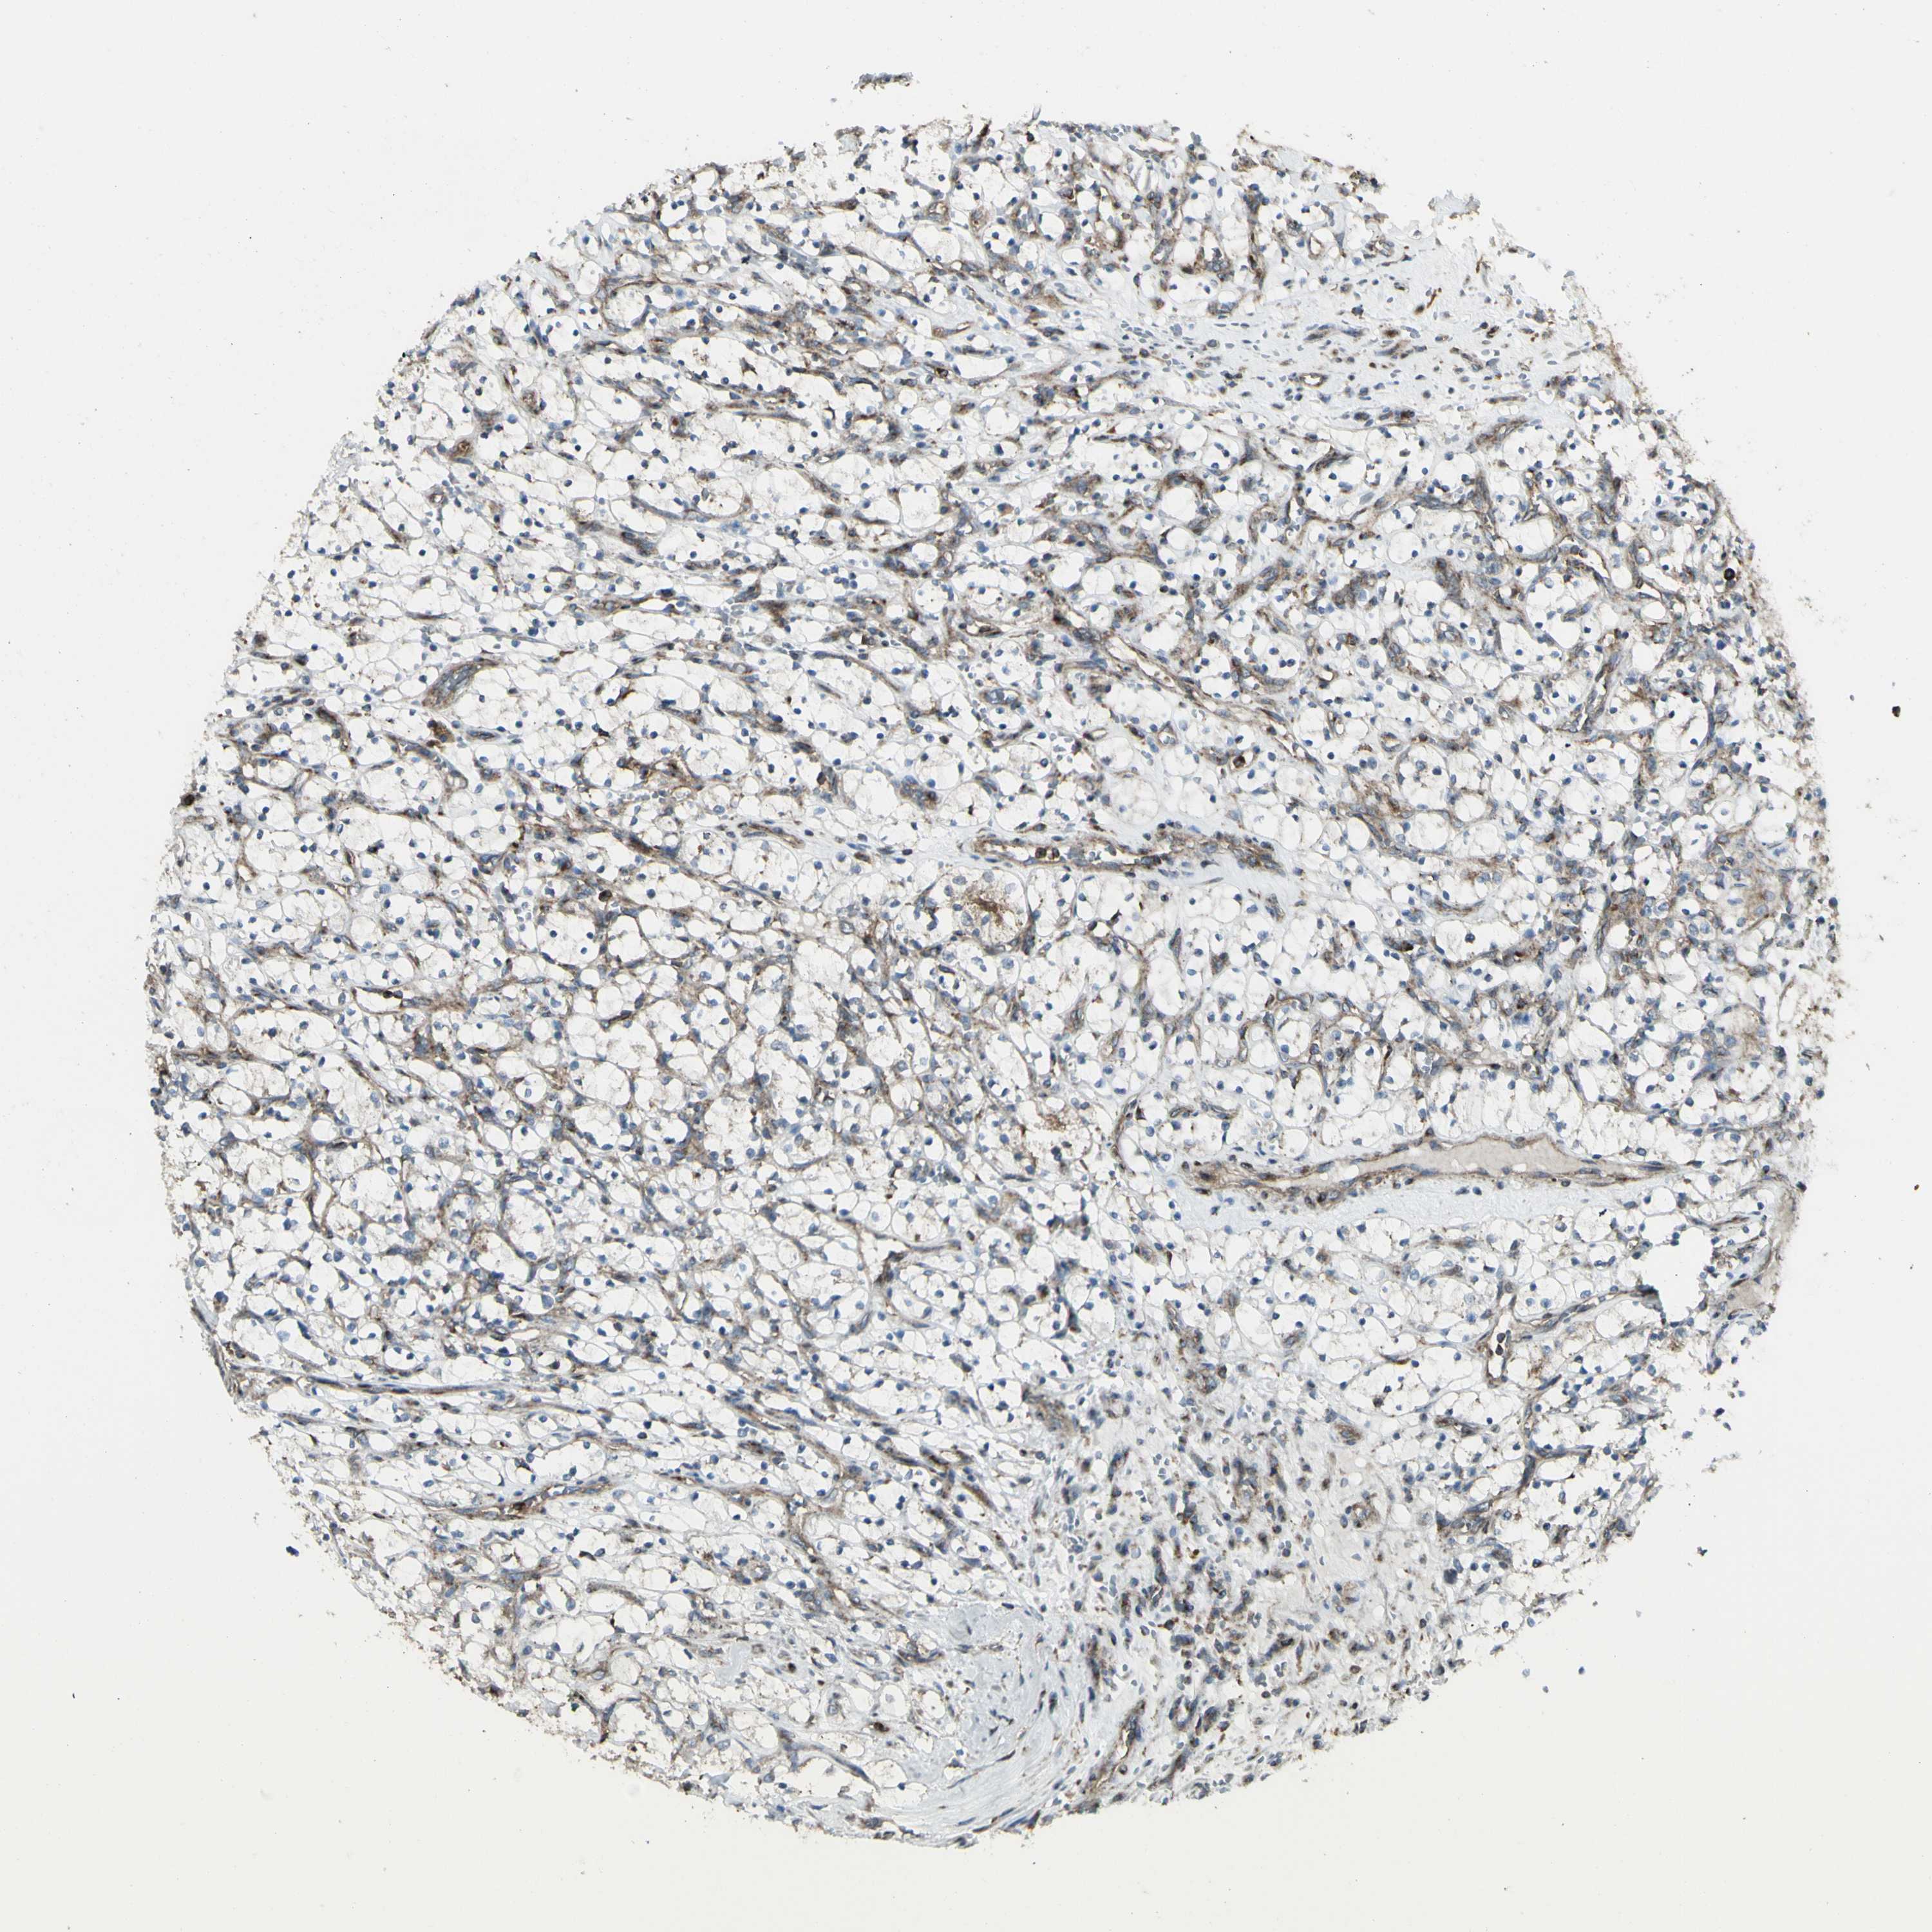

KIDNEY RENAL CLEAR CELL CARCINOMA (TCGA) - Interactive survival scatter ploti

The Survival Scatter plot shows the clinical status (i.e. dead or alive) for all individuals in the patient cohort, based on the same data that underlies the corresponding Kaplan-Meier plots. Patients that are alive at last time for follow-up are shown in blue and patients who have died during the study are shown in red.

The x-axis shows the expression levels (FPKM) of the investigated gene in the tumor tissue at the time of diagnosis. The y-axis shows the follow-up time after diagnosis (years). Both axes are complimented with kernel density curves demonstrating the data density over the axes. The top density plot shows the expression levels (FPKM) distribution among dead (red) and alive patients (blue). The right density plot shows the data density of the survived years of dead patients with high and low expression levels respectively, stratified using the cutoff indicated by the vertical dashed line through the Survival Scatter plot. This cutoff is automatically defined based on the FPKM cutoff that minimizes the p-score. The cutoff can be changed by dragging the vertical line or by entering a cutoff value in the square labeled "Current cut-off".

Under the Survival Scatter plot the p-score landscape (black curve; left axis) is shown together with dead median separation (red curve; right axis). Dead median separation is the difference in median mRNA expression between patients who have died with high and low expression, respectively. It is calculated as follows: median FPKM expression of dead patients with high expression - median FPKM expression of dead patients with low expression. This is intended to aid the user in visually exploring custom cutoffs and the associated p-scores and dead median separation.

Individual patient data is displayed and can be filtered by clicking on one or more of the category buttons on the top of the page. Categories describing expression level and patient information include: high, low, alive, dead, female, male and tumor stages. The scale of the x-axis can be toggled between linear and log-scale by clicking on the "x log" button. Mouse-over function shows TCGA ID, patient information and mRNA expression (FPKM) for each patient.

& Survival analysisi

Kaplan-Meier plots summarize results from analysis of correlation between mRNA expression level and patient survival. Patients were divided based on level of expression into one of the two groups "low" (under cut off) or "high" (over cut off). X-axis shows time for survival (years) and y-axis shows the probability of survival, where 1.0 corresponds to 100 percent.

NAPA is potential prognostic, high expression is favorable in Kidney Renal Clear Cell Carcinoma (TCGA)

Best expression cut offi

Based on the FPKM value of each gene, patients were classified into two groups and association between prognosis (survival) and gene expression (FPKM) was examined. The best expression cut-off refers the FPKM value that yields maximal difference with regard to survival between the two groups at the lowest log-rank P-value. Best expression cut-off was selected based on survival analysis .

When clicking on this number, the vertical dashed line indicating cut-off, the interactive survival plot, and the Kaplan-Meier curve will be adjusted to show results based on the best expression cut-off.

: 88.19

Average pTPM 112.1

Number of samples 521